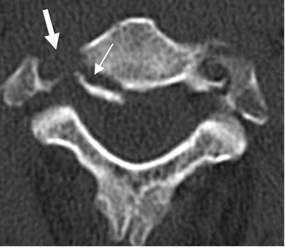

Fig 160. Fractura estable.

TAC axial. Fractura en la parte posterior del cuerpo, que corresponde a la columna media. (Flecha delgada). Igualmente hay fractura de la apófisis transversa, con compromiso del canal de la arteria vertebral. (Flecha gruesa).

Fig 161. Fractura estable.

A: TAC axial y B: TAC reconstrucción sagital. Fractura no desplazada de ambas láminas vertebrales, por lesión estable.